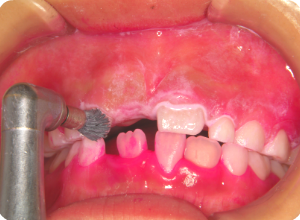

②磨き残しや汚れなどを、ブラシとラバーカップを使って落としていきます。

キレイになりました。